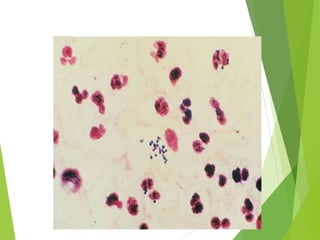

Definition  Acute jointinfection due to bacterial agents  Medical emergency

 Risk factors: Systemic:  Old age (>80 Y)  RA  DM  Immunosuppressive  Hemodyalisis  Malignancy  Local:  RA  OA  Prosthetic joint

Etiology (microbiology) Microbialagent:  Staphylococcus aureus: most common (75-80%)  Other organism in special patients:  Sexually active woman: Neisseria gonorrheae  Elderly, IV drug abuser, immunocompromised, UTI: Gram negative (p. aeruginosa and E.coli)  SLE: Salmonella  HIV: Pneumococci, Salmonella, H. influenzae  Alcoholism, Humeral immunity abnormality, Hemoglobinopathies: Pneumococcal infections  Primary immunoglobolin deficiency: Mycoplasma

Clinical manifestations  Fever(toxic)  Acute  Sever pain  Sever swelling of one joint  Sever tenderness  Warmth  Sever effusion  Sever limited ROM